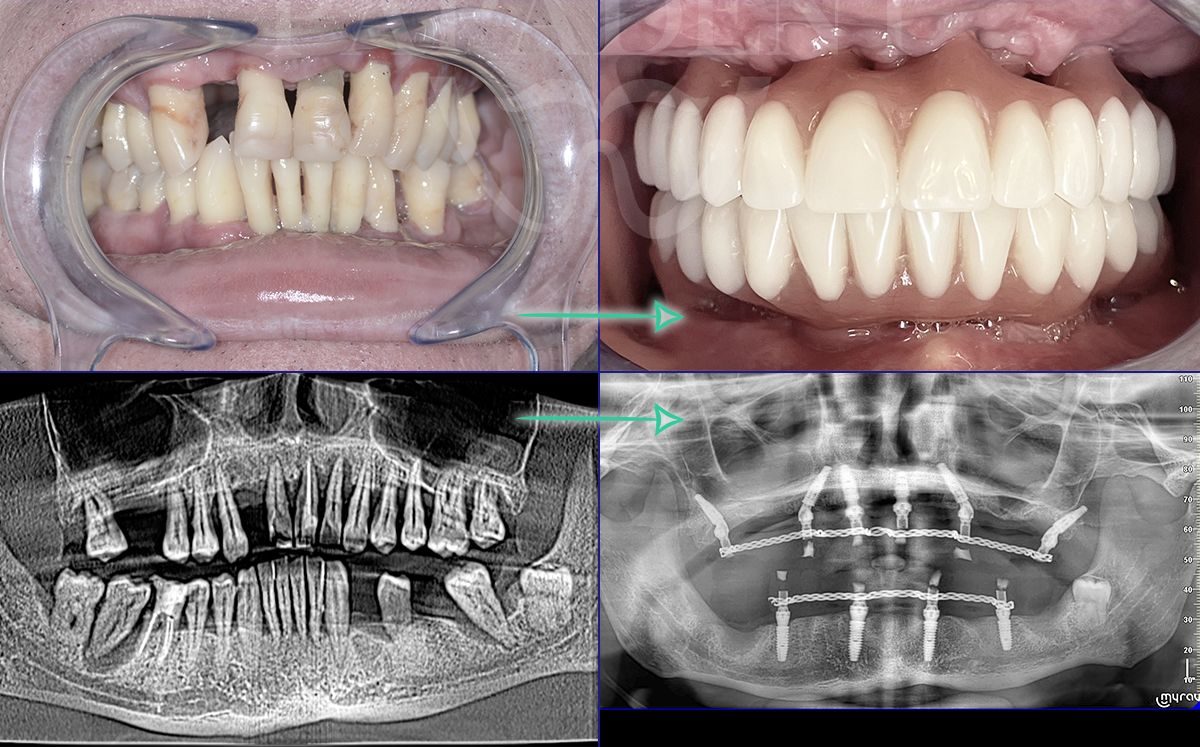

„All-on-4“ yra pažangi dantų implantavimo technika, leidžianti atkurti visą viršutinio arba apatinio žandikaulio dantų lanką vos su 4 implantais. Ant šių implantų fiksuojamas nuolatinis dantų protezas, kuris užtikrina ne tik estetišką šypseną, bet ir pilnavertę kramtymo funkciją. Šis metodas yra greitas, komfortiškas ir daugelio specialistų pripažįstamas kaip vienas efektyviausių sprendimų bedančiams žandikauliams netekus daugelio ar visų dantų.

- Dantų protezai ant 4 implantų vos per 24 – 48 val. Ir turite naujus visus dantis!